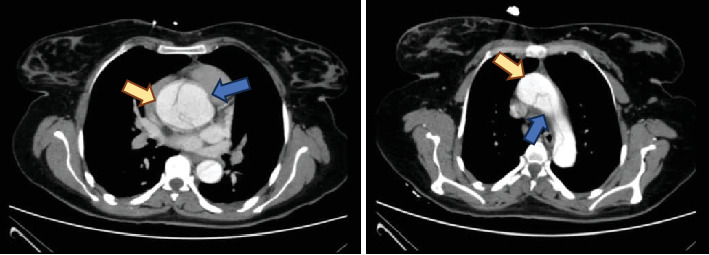

Aortic dissection (AoD) is a rare fatal condition in which tearing in the intima causes a false channel in the aorta and can lead to rupture. AoD is classified as the DeBakey classification (Types I, II, III) and Stanford classification (Types A and B). Women with underlying risk factors such as hypertension, smoking, bicuspid aortic valve, and connective tissue disorders are at risk for pregnancy-related AoD. These risk factors may not be recognized until the AoD occurs during pregnancy. We describe an acute incidence of type A AoD in the second trimester of pregnancy. A multiparous woman with no previously known risk factor presented with nonspecific chest pain. She was found to have AoD and underwent successful surgical intervention. This case demonstrates the importance of vigilance in the evaluation of pregnant women with new cardiopulmonary symptoms. A multidisciplinary approach can save the mother and the fetus.